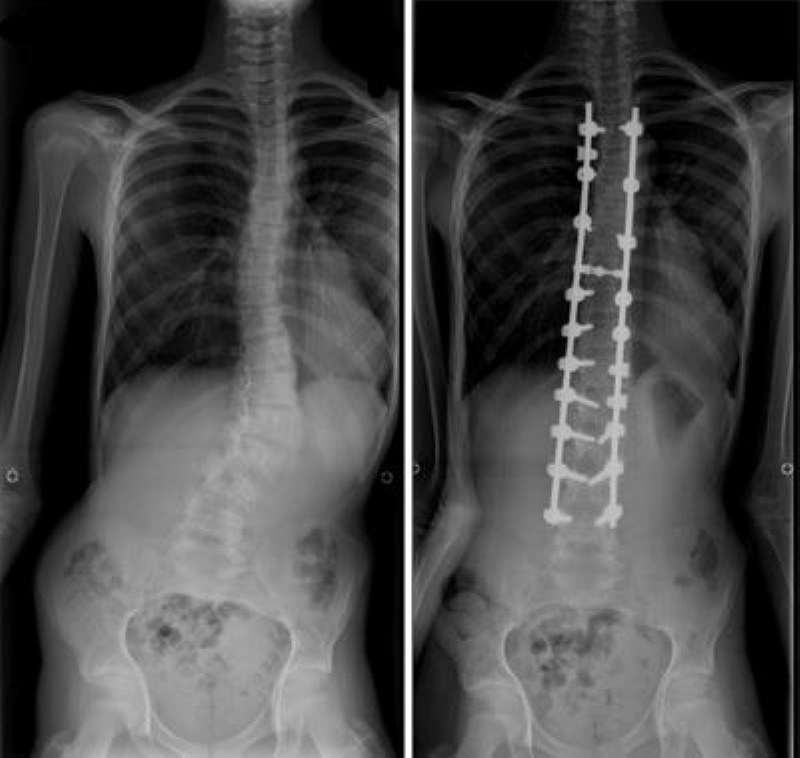

x-rays of scoliosis and spinal fusion

(Left) This x-ray shows scoliosis curves that require surgery. (Right) The same patient after surgery to correct the curves.